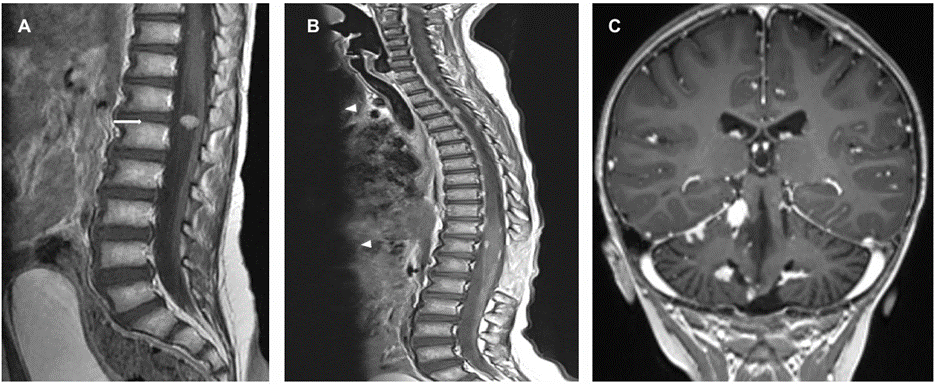

Post op brain MRI brain revealed improvement of the hydrocephalous and complete surgical resection of the mass with associated post-operative parenchymal changes and residual blood products within the operative cavity. Patient received 6 cycles of chemotherapy according of PNET 5 Protocol, consisting of 3 courses of cisplatin, CCNU and vincristine alternating with 3 courses of cyclophosphamide and vincristine. He also received radiotherapy as per standard risk protocol, with total of 55.8 Gy. The therapy was complicated by multiple episodes of febrile neutropenia. On regular follow up MRI scan 23 months post-resection, a solid enhancing lesion was noted along the cauda equina, to the right of the conus medullaris at T12-L1 (Figure 3), which was excised.

Figure 3: (a) Enhanced MRI spine showing the enhancing mass at the cauda equina (arrow). Follow up enhanced MRI of the spine (b) demonstrating the extramedullary enhancing lesions along the spine (arrowhead). (c) Coronal image along the cerebellum on the same MRI scan showing multiple enhancing lesions in the leptomeningeal distribution.

Four months later, other extramedullary spinal lesions also appeared on MRI along the spinal cord as well as multiple intracranial posterior fossa enhancing lesions in leptomeningeal distribution (Figure 3); the largest measured 1.3 cm. A spinal lesion was later excised to show similar pathology. The case released as “Drop metastasis of Medulloblastoma with complete myogenic differentiation”. Afterwards, there was interval progression in the size and distribution of the posterior fossa and spinal leptomeningeal metastasis. The patient became paraplegic and was started on second-line chemotherapy, however, the disease progressed while on therapy and the patient died of disease 30 months after his primary presentation.